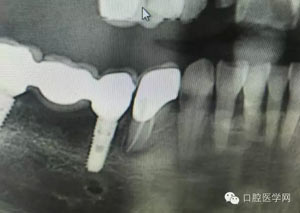

病例1:患者迫切希望保留自己的這一顆牙齒,根尖周陰影比較大,二度松動.而且旁邊有種植修復(fù)體,和患者溝通好后,治療好后觀察一個月后冠修復(fù),因為有種植的后期修復(fù),所以有了機會觀察,術(shù)后三個月和術(shù)后四個月,根尖恢復(fù)的還算不錯,希望能夠繼續(xù)觀察下去.這樣子的病例,做的時候我們一定要非常的小心,和患者要有充分的溝通以及不同科室的溝通然后決定怎么樣做比較好,假如就是出現(xiàn)了問題,到時候我們也比較好處理些,免得我們自己到時候不好收場。